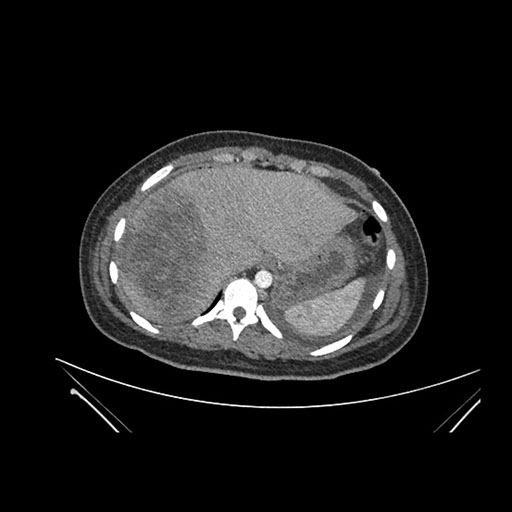

Imaging Analysis

Look through the patient's CT scan to identify any areas of concern for the necessary procedure.

Coronal Arterial

Based on initial findings, which issue(s) would you be most concerned about?